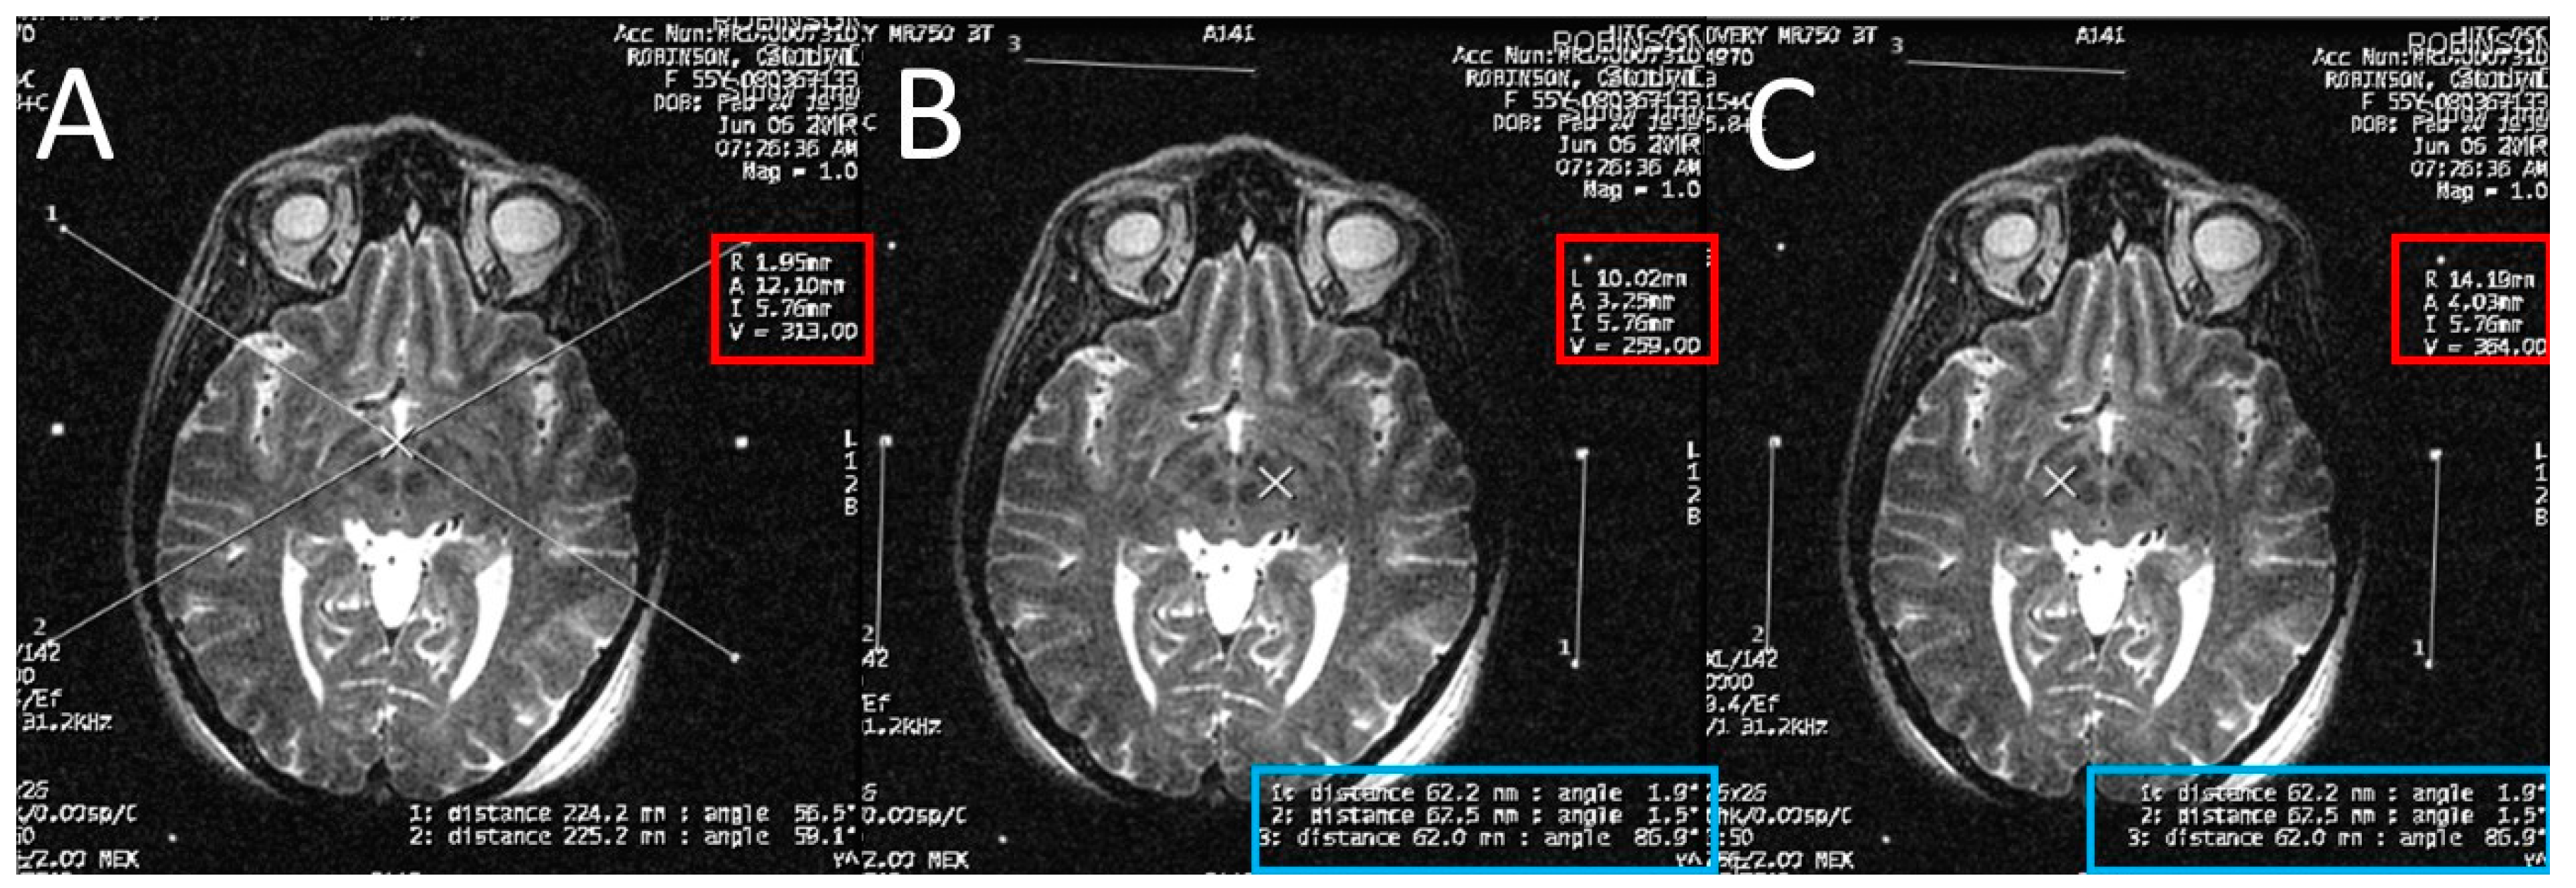

At the end of the scan, we chose an axial T2 image (or two adjacent images) in which both the AC and the PC are seen (Figure 3). With simple arithmetic equations based on the Leksell frame coordinates system, we were able to calculate the stereotactic coordinates of the mid-commissural point (MCP), and the STN directly from the MRI coordinates of the AC and the PC (Figure 4). Based on the known anatomical relationship of the STN to MCP from the previous anatomical studies and stereotactic atlases [36,47,48,49,50,51,52,53,54], we selected the STN target at 12 mm lateral, 3 mm posterior, and 6 mm inferior to the MCP.

Brainsci 06 00058 g003

Figure 4. Calculating the anterior commissure (AC) and posterior commissure (PC) coordinates using the magnetic resonance console. (A) Two diagonal lines intersecting at the center of the frame at the AC level with the magnetic resonance imaging (MRI) coordinates of the center of the frame shown inside the red square; (B) a crosshair at the posterior margin of the AC, with the MRI coordinates of the AC shown inside the red square. Two lines are drawn between the middle and the lower fiducials on both sides of the frame and their lengths (in the blue rectangle) are used to calculate the Z coordinate of the AC. (C) Two diagonal lines intersecting at the center of the frame at the PC level with the MRI coordinates of the center of the frame shown inside the red square; (D) a crosshair at the anterior margin of the PC, with the MRI coordinates of the PC shown inside the red square. Two lines are drawn between the middle and the lower fiducials on both sides of the frame and their lengths (in the blue rectangle) are used to calculate the Z coordinates of the PC.